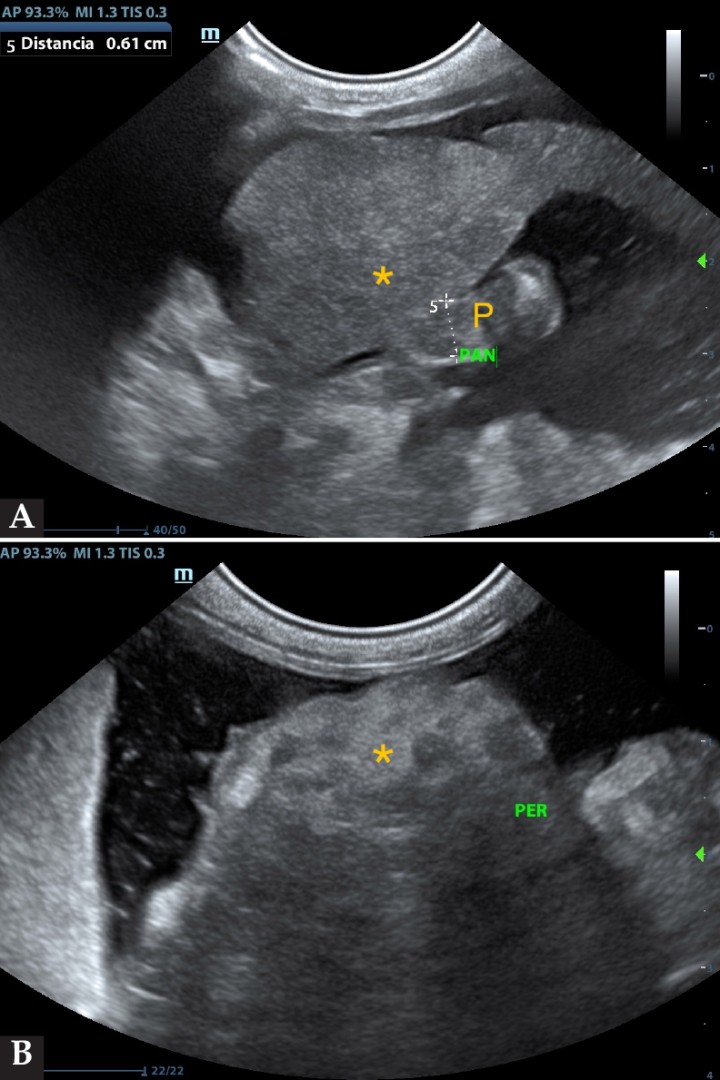

Se realizaron analítica sanguínea, proteinograma sérico y ecografía abdominal. En los resultados (Tabla 1) se observó trombocitosis (plaquetas: 639 x 103/µl, ref: 175-500 x 103/μl) leucocitosis con neutrofilia sin desviación a la izquierda y monocitosis (leucocitos: 26,7 x 103/µl, ref: 5,5-19,5 x 103/μl; neutrófilos: 20,8 x 103/µl, ref: 2,5-12,5 x 103/μl; monocitos: 2,6 x 103/µl, ref: 0-0,850 x 103/μl), hiperbilirrubinemia (bilirrubina: 0,60 mg/dl, ref: 0,1-0,5 mg/dl), hipocloremia (cloro: 110 mmol/l, ref: 115-128 mmol/l), hiponatremia (sodio: 143 mmol/l, ref: 148-157 mmol/l), hiperkalemia (potasio: 5,64 mmol/l, ref: 3,5-5,1 mmol/l), aumento AST (AST: 74 U/l, ref: 6-44 U/l) y disminución de urea (urea: 37 mg/dl, ref: 40-70 mg/dl). En el proteinograma (Fig. 1) se observó un aumento de las proteínas totales (proteínas: 82 g/l, ref: 55-71 g/l) con aumento de las alfa-2 globulinas (alfa-2 globulinas: 14,8 g/l, ref: 4-9 g/l) y disminución de las beta-globulinas (beta-globulinas: 8,1 g/l, ref: 9-19 g/l). Se realizó una ecografía abdominal en la que se observó abundante líquido libre abdominal y la presencia de una masa heterogénea en la zona pancreática, además del incremento de la ecogenicidad y aspecto heterogéneo del peritoneo, lesiones nodulares hepáticas, y efusión pleural escasa (Figs. 2 y 3).

<p>Presencia de líquido libre abdominal (*).</p>

Figura 2

Presencia de líquido libre abdominal (*).

<p>(<strong>A</strong>) Masa abdominal (*) asociada a la zona pancreática (P). (<strong>B</strong>) Masa abdominal de grandes dimensiones (*) y líquido libre abdominal.</p>

Figura 3

(A) Masa abdominal (*) asociada a la zona pancreática (P). (B) Masa abdominal de grandes dimensiones (*) y líquido libre abdominal.

La ecografía abdominal realizada en el paciente puso de manifiesto la presencia de abundante líquido abdominal libre, así como de una masa abdominal asociada a la zona pancreática. En gatos, el diagnóstico ecográfico de neoplasias pancreáticas puede ser complejo y en ocasiones difícil de diferenciar de otros procesos pancreáticos, como la hiperplasia, aunque la presencia de una masa mayor a 2 centímetros se ha relacionado con la presencia de neoplasia.[ Hecht S, Pennink DG, Keating JH: Imaging findings in pancreatic neoplasia and nodular hyperplasia in 19 cats. Vet Radiol Ultrasound 2007; 48: 45-50. [PubMed] ]